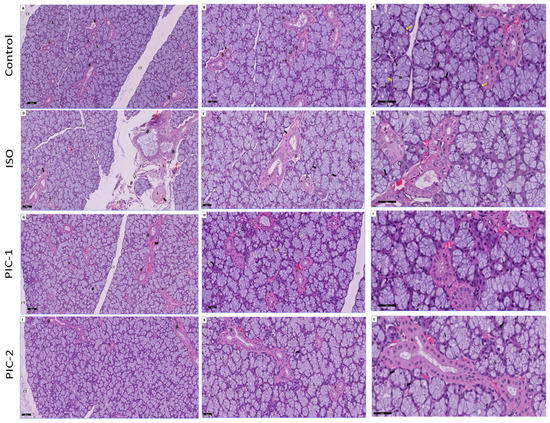

3.1.1. Examination of Hematoxylin and Eosin-Stained Sections

3.1.2. Examination of Masson Trichrome-Stained Sections